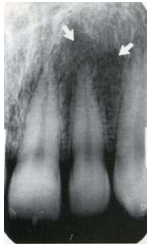

66.一位病患在根尖X光片攝影,發現側門齒根尖處有放射線透性(radiolucent)影像(如下圖白色 箭頭所指),臨床檢查左側正中門齒、側門齒及犬齒均具牙髓活性,此影像最可能為下列何者?

(A)Dentoalveolar abscess (B)Radicular cyst (C)Incisive foramen (D)Lateral fossa